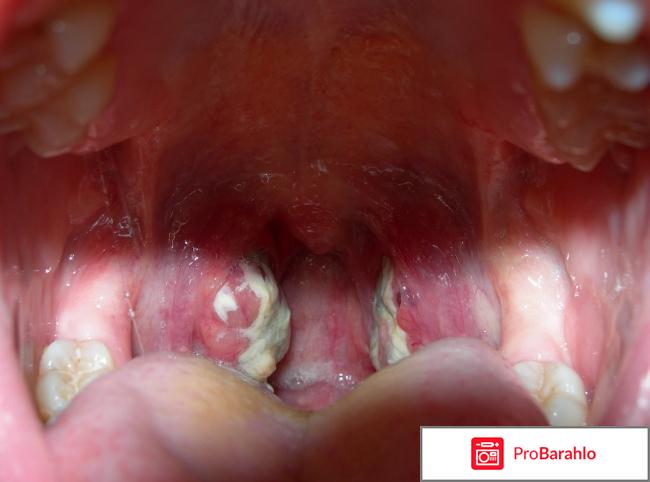

Привет всем, зима как известно пора не только снега и мороза, но и простуд ангин, фарингитов, ларингитов и других неприятных болезней. Однажды в дин из таких зимних дней я очень заболела. Сначала казалось бы. ну подумаешь горло болит, потом больно глотать, нагноения пошли, температура даже поднялась. Испугалась я не на шутку. Начала делать домашние примочки, полоскания и так далее. Мед в чай бросала, лимончик, даже сок свеклы пила и алое крутила на мясорубке и принимала с лимоном и медом как лекарство. Меня попустила, но, в организме то уже шел воспалительный процесс и я не знала как его снять. Подалась я в поликлинику. А там уже врач схватилась за голову и давай меня отчитывать как маленькую девчонку. Выписала она полоскание горла фуроцилином и мне цефтриаскон. Назначила колоть его по одной ампуле в день в течении пяти дней. Но предварительно разводить цефтриаксон с двухпроцентным новокаином и уколы вводить медленно внутримышечно. Это хорошо, что я сама уколы могу делать, а так бы пришлось с ангиной, да еще и с гнойной бегать в поликлинику на укол. Цефтриаксон очень хороший антибиотик, он лечит как в инструкции написано даже от гонореи!